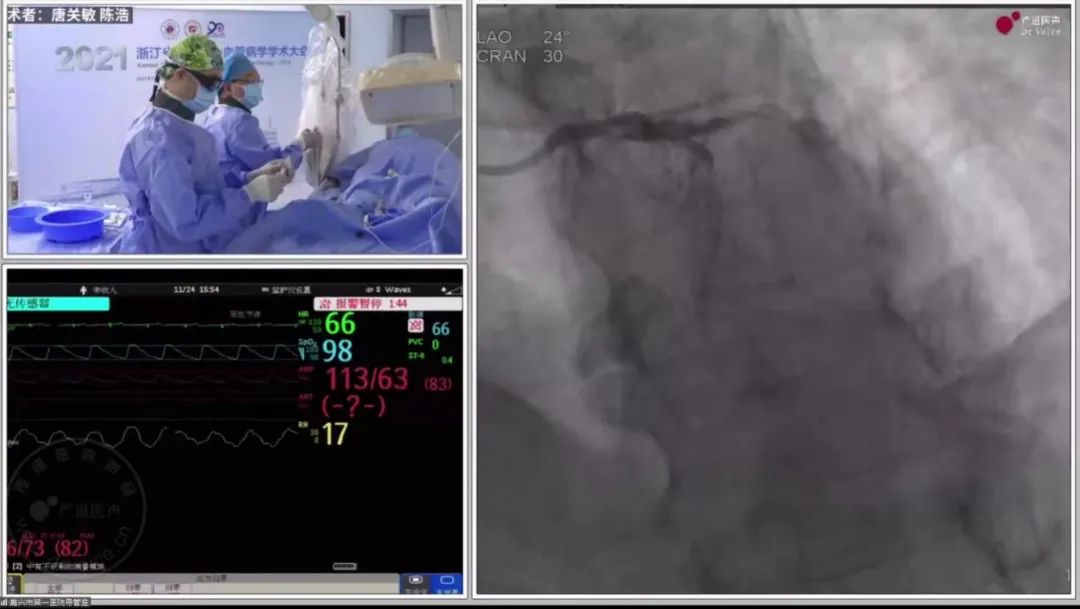

嘉兴市第一医院唐关敏教授团队带来两例高难度冠脉复杂病变病例演示。

图片

唐关敏教授团队手术直播中

其中一例为处理左主干前三叉病变,唐教授团队根据患者既往病史,仔细检查患者目前病变状态,经过深思熟虑,最终决定在手术中选用主支支架、分支药物球囊扩张技术,避免分叉部位过多金属小梁覆盖,优化了血运重建策略。整台手术进行有条不紊,最终顺利完成,患者术后各项指标显示良好。